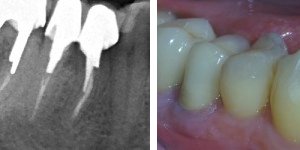

Na czym polega premolaryzacja?  Jest to przecięcie wzdłuż zęba trzonowego, z reguły dolnego, na dwie części tak aby powstały dwa przedtrzonowce (zdjecie poniżej)

Jeśli przeleczony kanałowo ząb jest wrażliwy a zdjęcie rentgenowskie wykazuje defekt kostny w obrębie bifurkacji  czyli w miejscu rozdzielenia korzeni, wszystko wskazuje na to, że dno komory zęba jest zniszczone, a nieszczelnośc ta spowodowała zniszczenie kości w tym miejscu. Zachowawcze leczenie jest niemożliwe.

Jeśli chce się uratowć taki ząb, jedynym rozwiązaniem jest separacja czyli premolaryzacja. Zabieg ten wykonuje się w znieczuleniu miejscowym. Wiertłem przecina się ząb, tak by odsłonić całą perforację dna komory. Stwarza się w ten sposób dwa oddzielne zęby. Miejsce przecięcia należy bardzo dokładnie i szczelnie zabezpieczyć kompozytem. Jest to dość trudne w wilgotnym, podziąsłowym miejscu. Jeśli leczenie kanałowe jest nieszczelne należy je wykonać ponownie.

Poniżej zdjęcie rentgenowskie po zabiegu premolaryzacji. Widzimy już dwa oddzielne zęby.